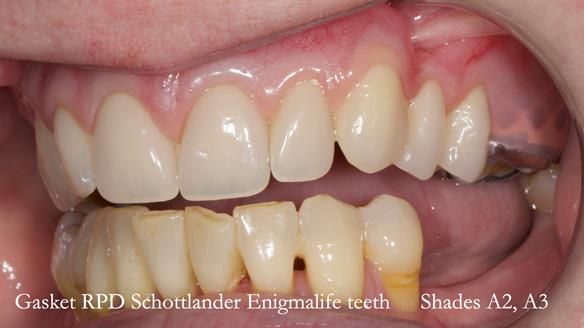

Welcome to my Newsletter 58, where I show the making and fitting of an upper gasket partial denture for Zoe (52 year old woman). This issue provides a comprehensive overview of the entire protocol workflow for this superbly retained denture.

Zoe was referred to me for specialist prosthodontics by her general dentist, after unsuccessful attempts to provide a denture because of fractures, looseness and discomfort.

Natural appearance – just like my natural teeth.

I do not want anyone knowing I use a denture.

The detailed clinical situation and treatment process are outlined below, with clinical work provided by me and technical work by Rowan Garstang. The treatment spanned five visits for denture fitting and one review.